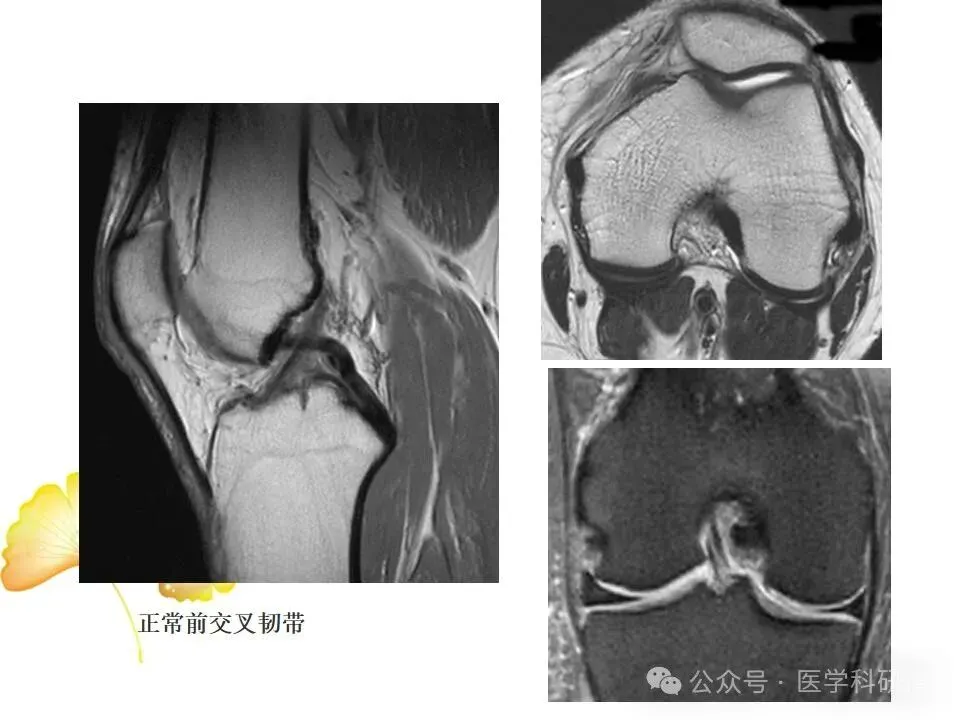

• 前交叉韧带(ACL):位于膝关节内部,负责防止胫骨向前滑动以及控制膝关节的旋转运动。

当膝关节遭受剧烈撞击或扭伤时,上述韧带可能发生拉伤、部分撕裂或完全撕裂,其中ACL损伤最为常见。韧带损伤会导致膝关节稳定性降低,影响日常活动和运动表现。

二、MRI在膝关节韧带损伤诊断中的应用详解

MRI是一种先进的医学成像技术,能够提供高分辨率的膝关节图像,对韧带损伤的诊断具有重要价值。MRI检查可以采用不同的成像技术,如: